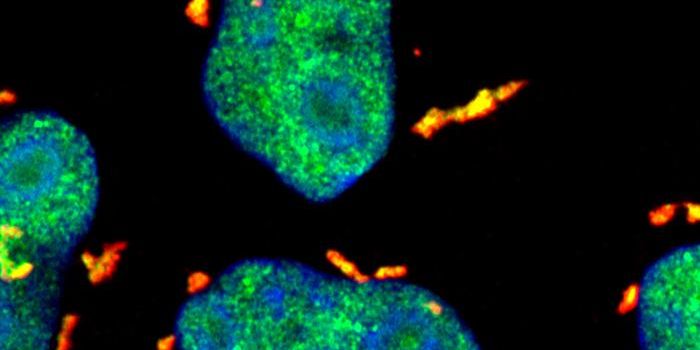

SEP 05, 2024Cell & Molecular BiologyCorynebacterium matruchotii ia a common bacterium that lives in human dental plaque; a colony is seen in this image by S ...

AUG 26, 2024Clinical & Molecular DXA colorized scanning electron micrograph depicts a Kupffer cell. / Credit: Thomas Deerinck, National Center for Microsco ...

AUG 16, 2024MicrobiologyAnimal models have served as excellent models of many aspects of human biology and disease, but they cannot mimic every ...